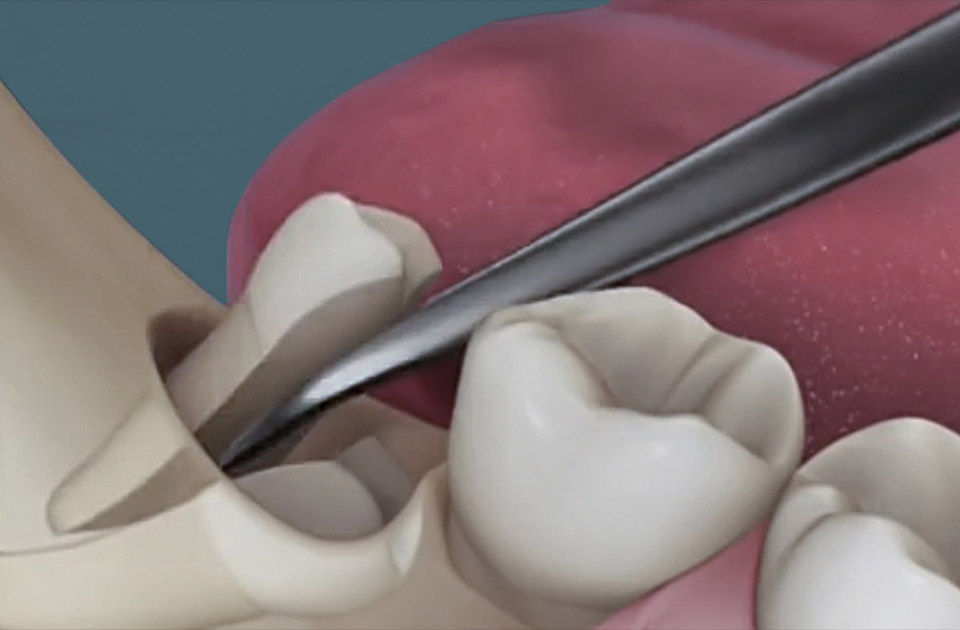

بیهوشی: در بیشتر موارد ، برداشتن دندان های دندانی شدید تحت بیهوشی موضعی انجام می شود. ابتدا لثه بیمار با ژل بیهوشی درمان می شود تا محل تزریق بی حس شود ، سپس تزریق می کنیم. پس از 3-5 دقیقه ، هنگامی که لثه ها ودندان تحت بیهوشی منجمد می شوند قرار می گیرند ، می توان دندان را برداشته ، در حالی که بیمار احساس درد نمی کند.

کشیدن دندان: دندانپزشک دندان مولر را با ابزار مخصوص می گیرد و از سوراخ خارج می کند. با یک استخراج ساده ، کشیدن دندان عقل یک کار چند ثانیه ای است. ما در مورد تفاوت های ظریف حذف پیچیده بیشتر به شما خواهیم گفت.سوراخ با یک محلول ضد عفونی کننده درمان می شود ، در صورت لزوم ، لبه های آن بخیه می شوند.

استخراج آنها همیشه تحت بیهوشی انجام می شود. بیهوشی موضعی اغلب برای این کار انجام می شود ، در برخی موارد آرام بخش و حتی بیهوشی عمومی استفاده می شود. به لطف استفاده از مسکن های مدرن با سرعت بالا ، بیمار هیچ دردی احساس نمی کند. عمل برداشتن دندان عقل با معرفی یک بیهوشی آغاز می شود: قبل از کشیدن دندان عقل ، دندانپزشک غشای مخاطی را با ژل بیهوشی درمان می کند و سپس تزریق بیهوشی می کند. به عنوان یک قاعده ، تزریق از دو طرف بیرونی و داخلی انجام می شود. پس از 4-5 دقیقه ، هنگامی که بیهوشی اثر می گذارد ، می توانید "دندان عقل" را بردارید ، بیمار دردی را احساس نخواهد کرد.